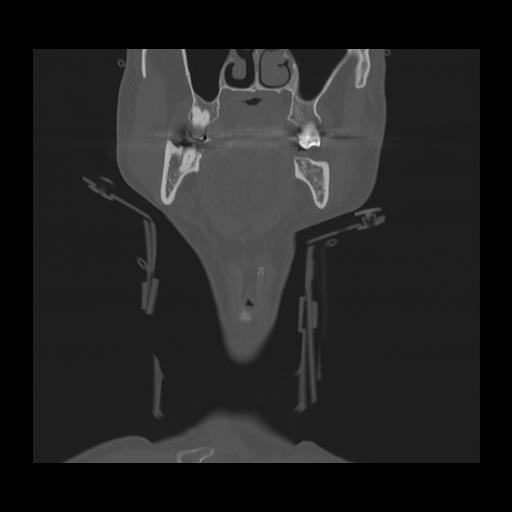

16 HUESO,,Coronal,2.000,HUESO,Coronal,